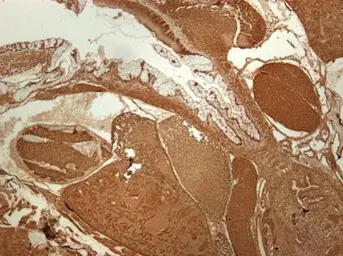

Immunohistochemical analysis of paraffin-embedded zebrafish tissue, using RPS3A antibody (GTX111935) at 1:300 dilution.